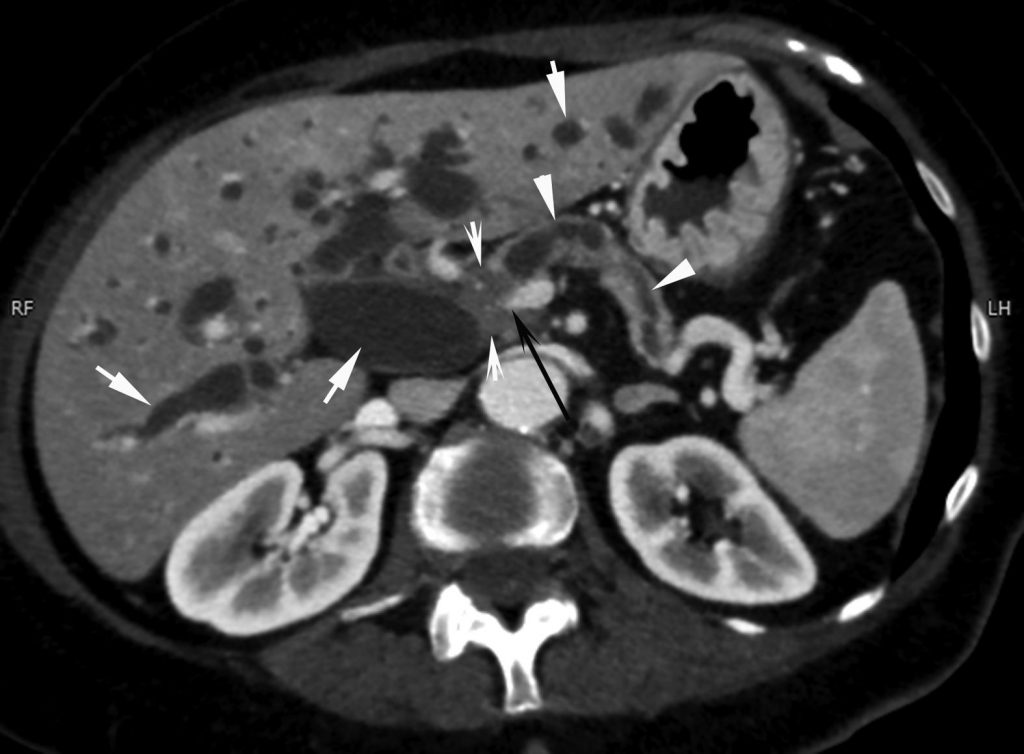

Au scanner, la tumeur peut être difficile à voir, souvent non visible avant injection de produit de contraste iodé. Après injection, la glande normale se rehausse plus que la tumeur, qui apparaît hypodense (figure 18.2).

Du fait de la difficulté de voir directement la tumeur, les signes indirects sont donc très importants à rechercher pour ne pas méconnaître la lésion, facilement visibles en échographie, au scanner (figure 18.3) ou en IRM (figure 18.4) :

- la dilatation du conduit pancréatique principal si la tumeur se situe sur le corps ou la queue du pancréas avec, dans ce cas, de possibles épisodes de pancréatite aiguë ;

- et/ou la dilatation des voies biliaires si la tumeur est développée dans la tête du pancréas. Dans ce cas, les examens d’imagerie montrent une dilatation des voies biliaires intra- et extrahépatiques et une grosse vésicule biliaire (hydrocholécyste). Il y a souvent un ictère associé sans fièvre (ictère nu).

Fig. 18.3. Examen tomodensitométrique d’un pancréas tumoral. TDM après injection de produit de contraste iodé montrant une dilatation du conduit pancréatique (têtes de flèches) associée à une atrophie de la glande pancréatique. On observe également une dilatation marquée des voies biliaires intra- et extrahépatiques et de la vésicule (flèches). Le conduit cholédoque mesure ici plus de 20 mm de diamètre. La flèche noire montre une sténose de la terminaison de la veine mésentérique supérieure, envahie par la tumeur.

Source : CERF, CNEBMN, 2022.